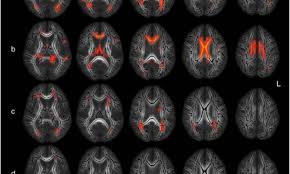

Diese Aussackungen der Hirngefäße sind oft sehr klein. Es ist davon auszugehen dass etwa 15 bis 5 Prozent der Bevölkerung im Laufe des Lebens ein Hirnarterienaneurysma entwickeln ohne dass es zwangsläufig zu Symptomen kommt. Aber es lässt sich nicht ganz ausschließen dass auch solche kleinen Aneurysmen reißen.

Ein Aneurysma vor allem im Gehirn kann angeboren sein. Da das Schiff beginnt sich aufzublähen wird es wahrscheinlicher zu platzen. Niemand kann vorhersagen wann ein Aneurysma platzt und Leck Blut in die umliegenden Gebiete. Solange ein Aneurysma noch klein und intakt ist das Gefäß also keine Risse hat verursacht es häufig keinerlei oder nur unspezifische Beschwerden wie Kopfschmerzen oder Übelkeit. Wenn ein Blutgefäß erweitert oder Ballons durch Schwächung Wände heißt es ein Aneurysma. Je nach Größe und Lage des Aneurysmas im Gehirn können jedoch auch Beschwerden auftreten. Ein Aneurysma ist eine krankhafte Aussackung einer Schlagader. Fachleute gehen aber davon aus dass Aneurysmen mit einem Durchmesser unter sieben Millimetern nicht sofort behandelt werden müssen sondern beobachtet werden können. Je nach Größe und Ort sind weitere Symptome möglich.

Nicht rupturierte intrakranielle Aneurysmen finden sich bei etwa drei Prozent der Erwachsenen. Ein Aneurysma ist eine krankhafte Gefäßausstülpung also eine örtlich begrenzte Erweiterung einer Arterie. Ein Aneurysma ist eine krankhafte Gefäßausstülpung die sich an den hirnversorgenden Gefäßen zumeist an Gefäßaufzweigungen befindet. Die meisten Gefäßaussackungen im Kopf entdecken Ärzte durch Zufall oder weil sie Symptome wie beispielsweise Doppeltsehen verursachen. Täglich im Kühlschrank aufbewahren. Aber es lässt sich nicht ganz ausschließen dass auch solche kleinen Aneurysmen reißen. Niemand kann vorhersagen wann ein Aneurysma platzt und Leck Blut in die umliegenden Gebiete.